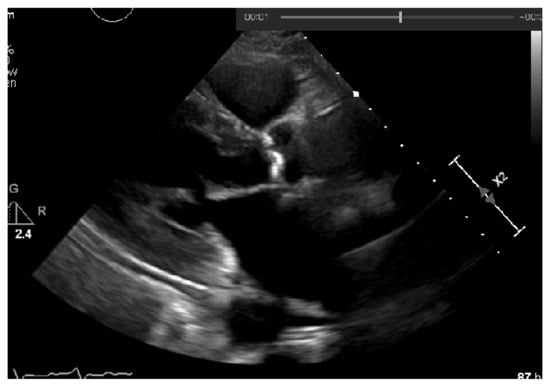

To the resulting images of this blurring phase, a binarization operation with a fixed pixel threshold value of 160 was produced, experimentally obtained by analyzing 48 cases of echocardiography images, where 255 corresponds to calcium, as seen in Figure 5. This initial approach of a using a fixed threshold is not sufficient for our problem at hand, since our images’ brightness may vary, given different data collection conditions. To tackle this issue, an adaptive binarization technique has to be performed, which will be further explained.

In Figure 5, it is noticeable that when the blurring parameter increases from 5 to 11, we get a cleaner image (without small white dots—noise). However, we can also notice that in the region of interest (marked with red circles), when the blur increases, we lose pixels, since the region gets smaller. To mitigate this, a mask dilation operator was applied to each region of interest.

As shown Figure 6, the pixels lost in the blurring phase can be recovered by applying the dilation mask to the regions of interest in the image.

Figure 5. Binarization of an echocardiography image, for each size of the kernel parameter applied—The red circle represents our ROI (aortic valve).

Figure 6. Application of the dilation mask to the regions of interest of the image, in order to recover the pixels lost in the blurring phase.